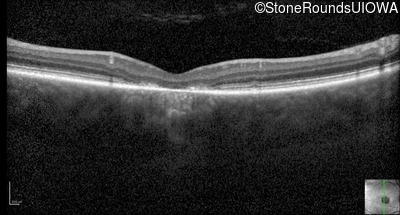

Optical Coherence Tomography - Right - 20/125 -1

Exemplar / OCT Stack